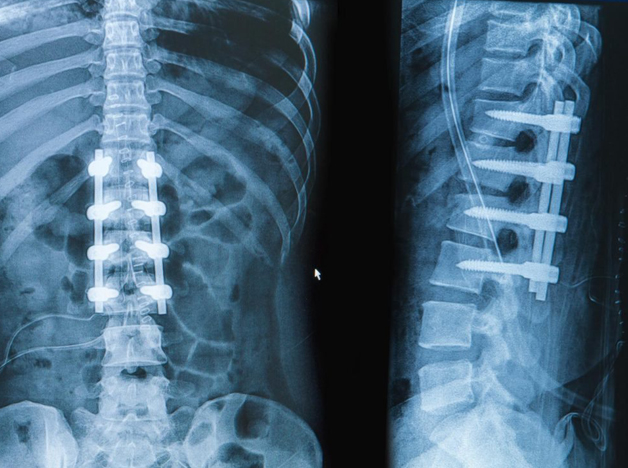

Vertebral Fusion

In some cases, instability of the spine might be detected, which may require a posterior fusion of the spine. In the fusion procedure, a bone graft (from your pelvis or spine) is taken, or a synthetic bone graft can be used around the spine to create a solid bony fusion across the unstable segments. In most cases, titanium screws and rods are placed to increase the stability, and sometimes the lumbar disc is removed and replaced with a plastic cage filled with bone graft.